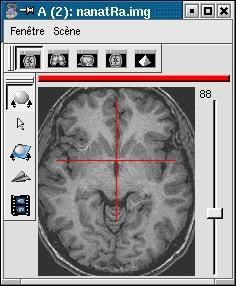

- SHFJ from SPM: minimal field of view, resolution 1x1x1mm

![]()